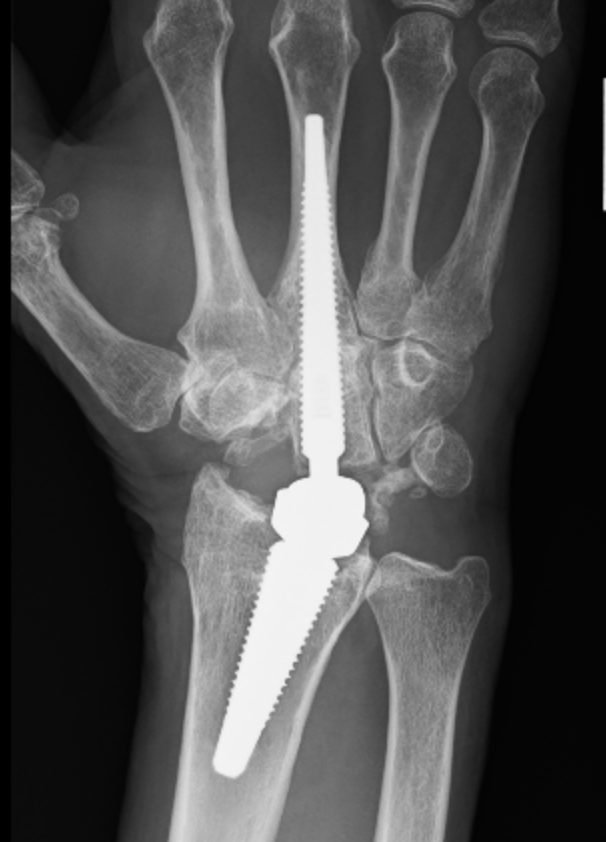

Galeazzi fractures

Fracture of the radial shaft with disruption to the distal radio-ulna joint (DRUJ)